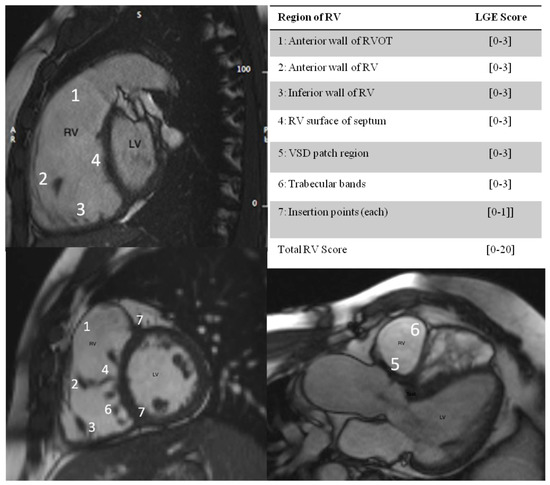

We found that longitudinal strain analysis by CMR-FT of the LV was impaired in adults with rToF, despite the preserved LV EF and correlation with high RV fibrosis score. According to the normal values for ages <75 years old of the non-HF population (<125 pg/mL), mean values of NTproBNP levels in our study were increased (181.2 ± 178.4 pg/mL), with preserved LV EF. NTproBNP levels correlated significantly with high RV fibrosis score. In ROC curve analysis, a cut-off value of NTproBNP > 145pg/mL and a cut-off value of GLS LV −15.9% predicted LGE RV >8 points, reflecting the coexistence of the LV longitudinal systolic dysfunction due to ventricular–ventricular interaction and neurohormonal activation, as result of high RV fibrosis (Figure 3).

Figure 3.

In ROC curve analysis, a cut-off value for NTproBNP of 145.25 pg/mL predicted LGE RV score > 8 points with specificity 80% and sensitivity 73.3% [AUC 0.729 (p = 0.03)], and a cut-off value for LV GLS of −15.9% predicted LGE RV score > 8 points with specificity 80% and sensitivity 69.2% [AUC 0.754 (p = 0.02)].